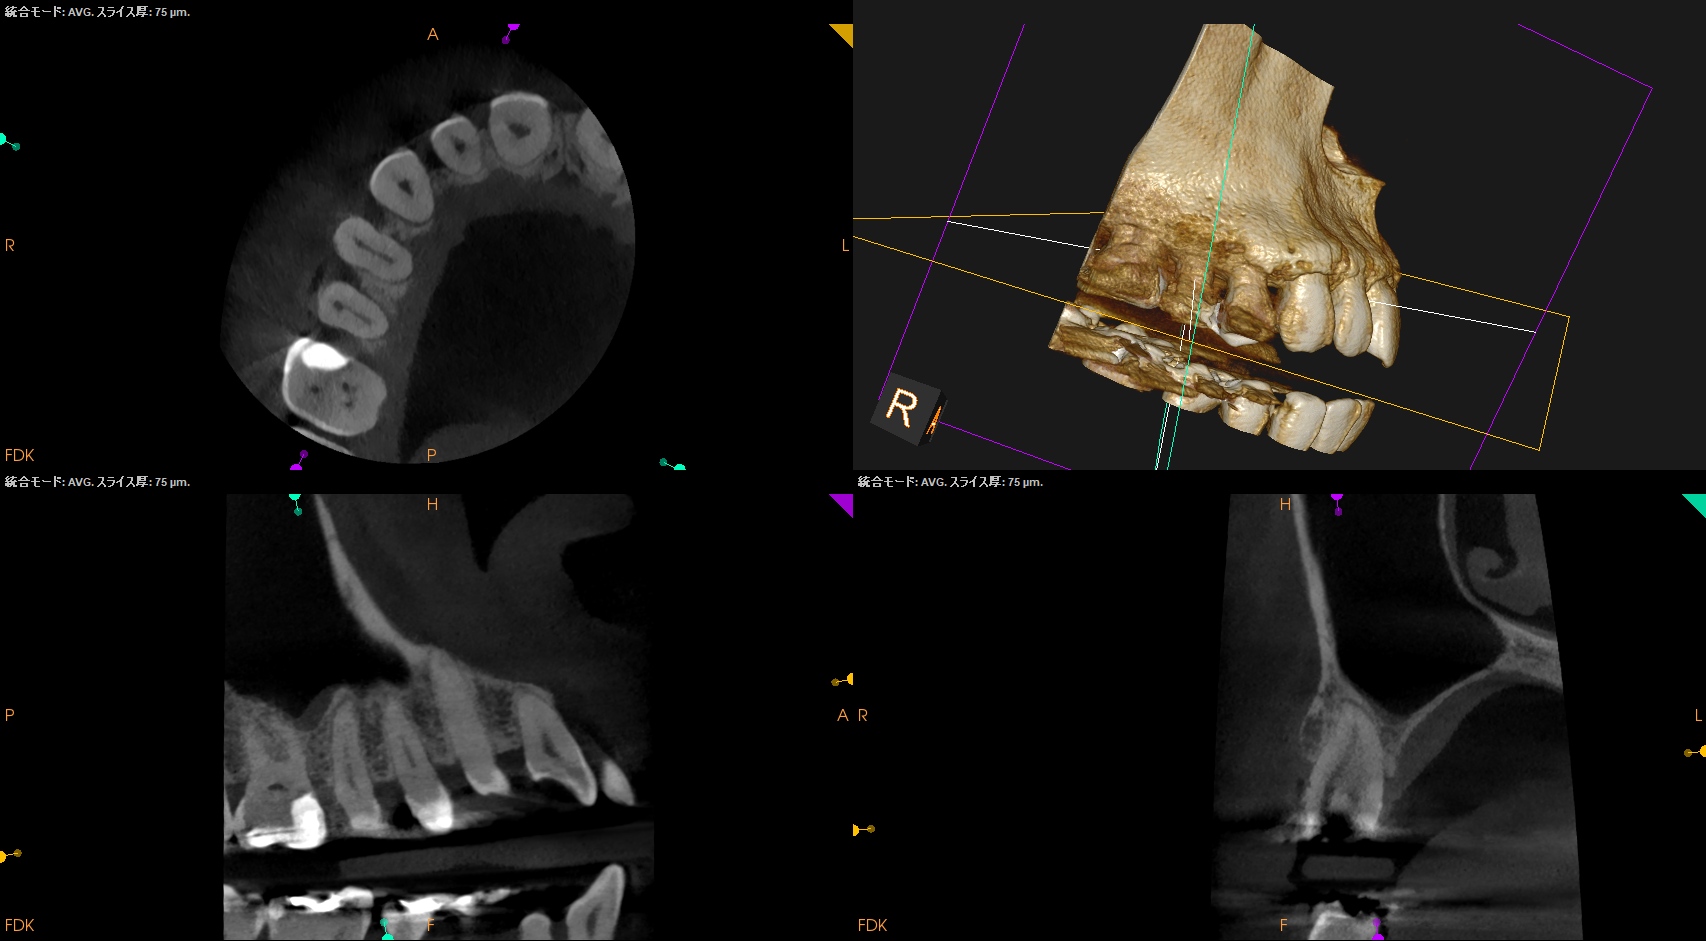

Pre-op Endo test(2025.11.26)

#4に咬合痛があるような…ないようなという感じであった。

病変のない、Initial RCTだ。

Pulp Dx: Asymptomatic irreversible pulpitis

Periapical Dx: Symptomatic apical periodontitis

Recommended Tx: RCT

術後にPA, CBCTを撮影した。